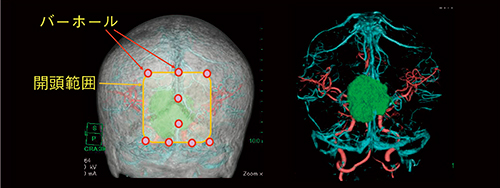

図6 フュージョン画像による手術支援

頭蓋内腫瘍摘出術(髄膜腫)における単純CTと造影CTから作成したフュージョン画像を示す。